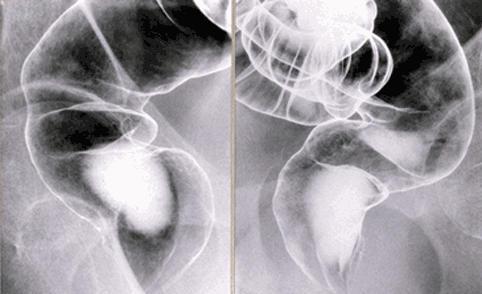

疾患(病理主体)の分類炎症性・潰瘍性疾患/直腸粘膜脱症候群

部位(臓器別)大腸/直腸

検査方法X-P

病変の最大径(ミリ)20〜24